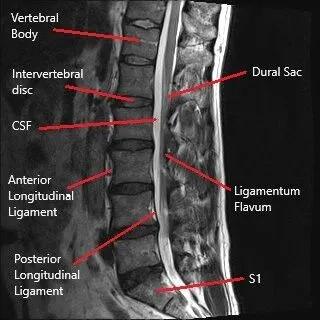

PreoperativeEvaluation:Carefulreviewofcross-sectional images(MRIorCT)toassesstheavailableepiduralspace, thicknessoftheligamentumflavum(LF),andpotential mechanicalimpedimentstoinstrumententry

Arecommendedimaging techniqueforassessing theinterlaminarspace involvesobtainingan anteroposterior(AP) imagewherethe vertebralendplatesare squaredwiththe fluoroscopicbeam.